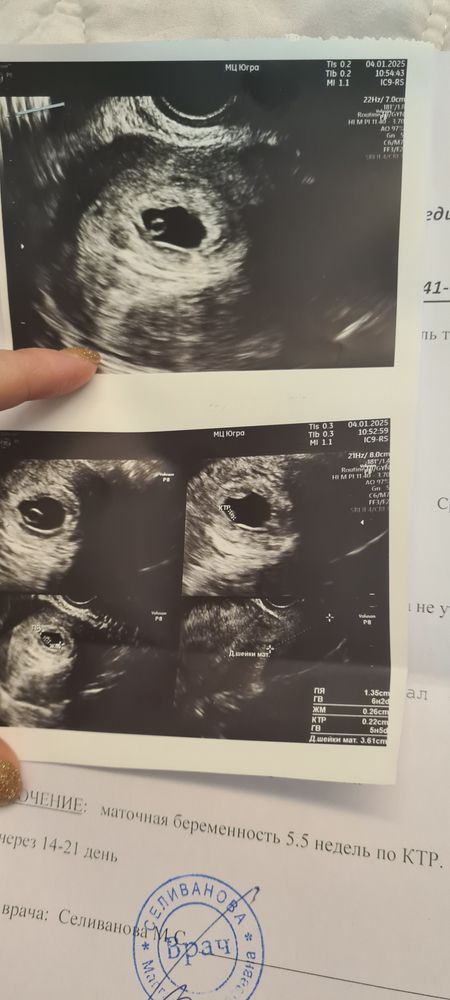

Девочки подскажите. У меня ЭКО, подсадка была 02.12.2024 г. 5 дневного эмбриона. На узи ходила 27.12 эмбриона не увидели, сказали сходить через неделю. Сделала повторное узи 04.01.2025 вот такой результат. Подскажите ктр ставят 0.22 см это не слишком ли маленький эмбрион для такого срока? 1-2 фото узи от 27 числа, третье от 4.

Свет в окошке, врач конечно мне сказала что это норма, но что то у меня все равно есть сомнения(

Свет в окошке, все будет хорошо, у нас сердце бьется его видно. Меня просто сам размер не много пугает, вроде он должен быть уже 1 см но так пишут в интернете. Вы главное не переживайте вам это сейчас совсем лишнее🤗